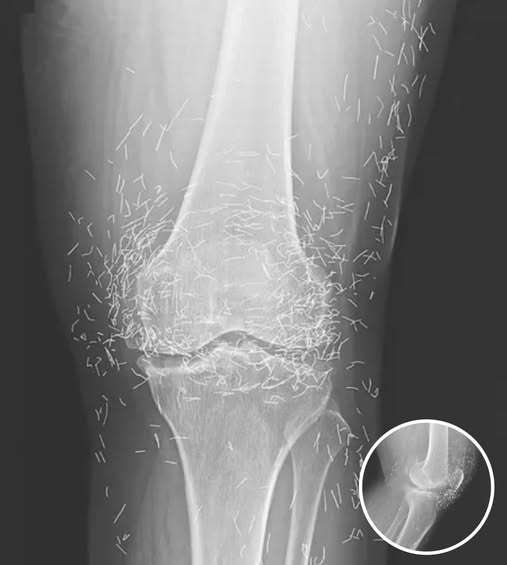

Doctors Stunned After Looking At This X-Ray Of Woman Suffering Joint Pain…More Details below

A 65-year-old woman in South Korea experienced a shocking medical discovery when doctors found hundreds of tiny gold needles embedded in her knee tissue during a routine X-ray. She had been suffering from chronic osteoarthritis,… Read more